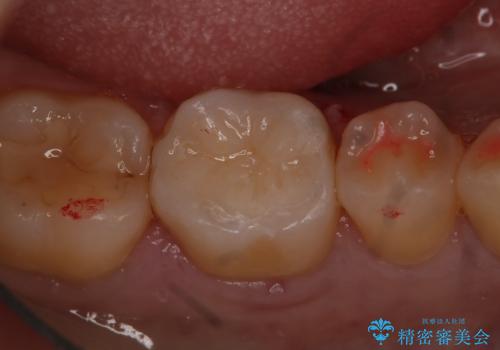

詰め物が外れかけてるのでやり替えたい セラミックインレー修復・フルジルコニアクラウン